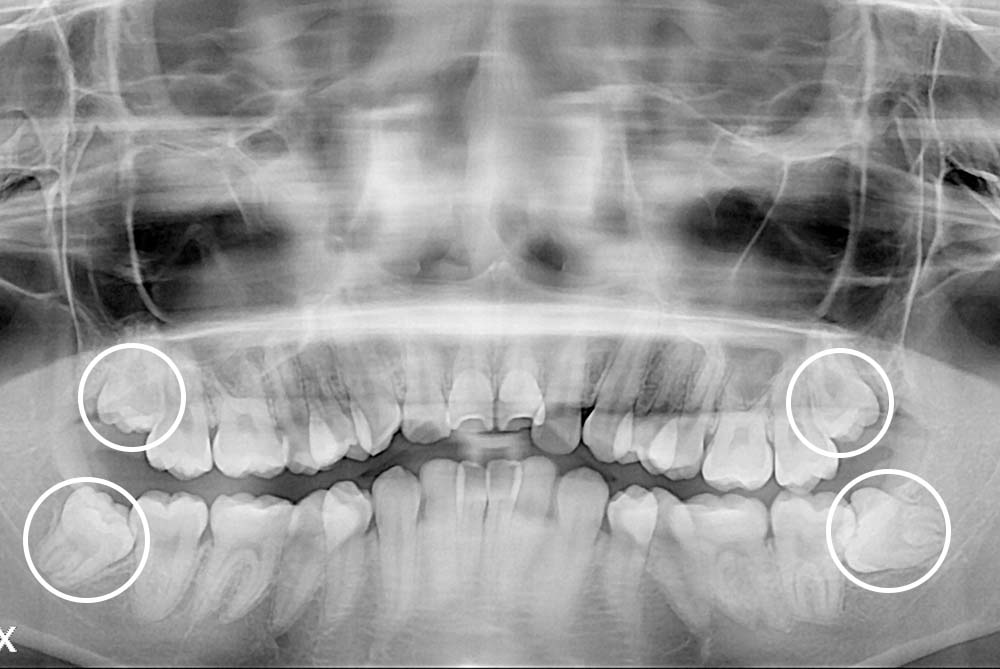

[사랑니] 매복 사랑니 발치

치료후 : 2023-01-06

세종치과는 구강악안면외과학 박사이신 원장님이 발치하는 치과입니다.